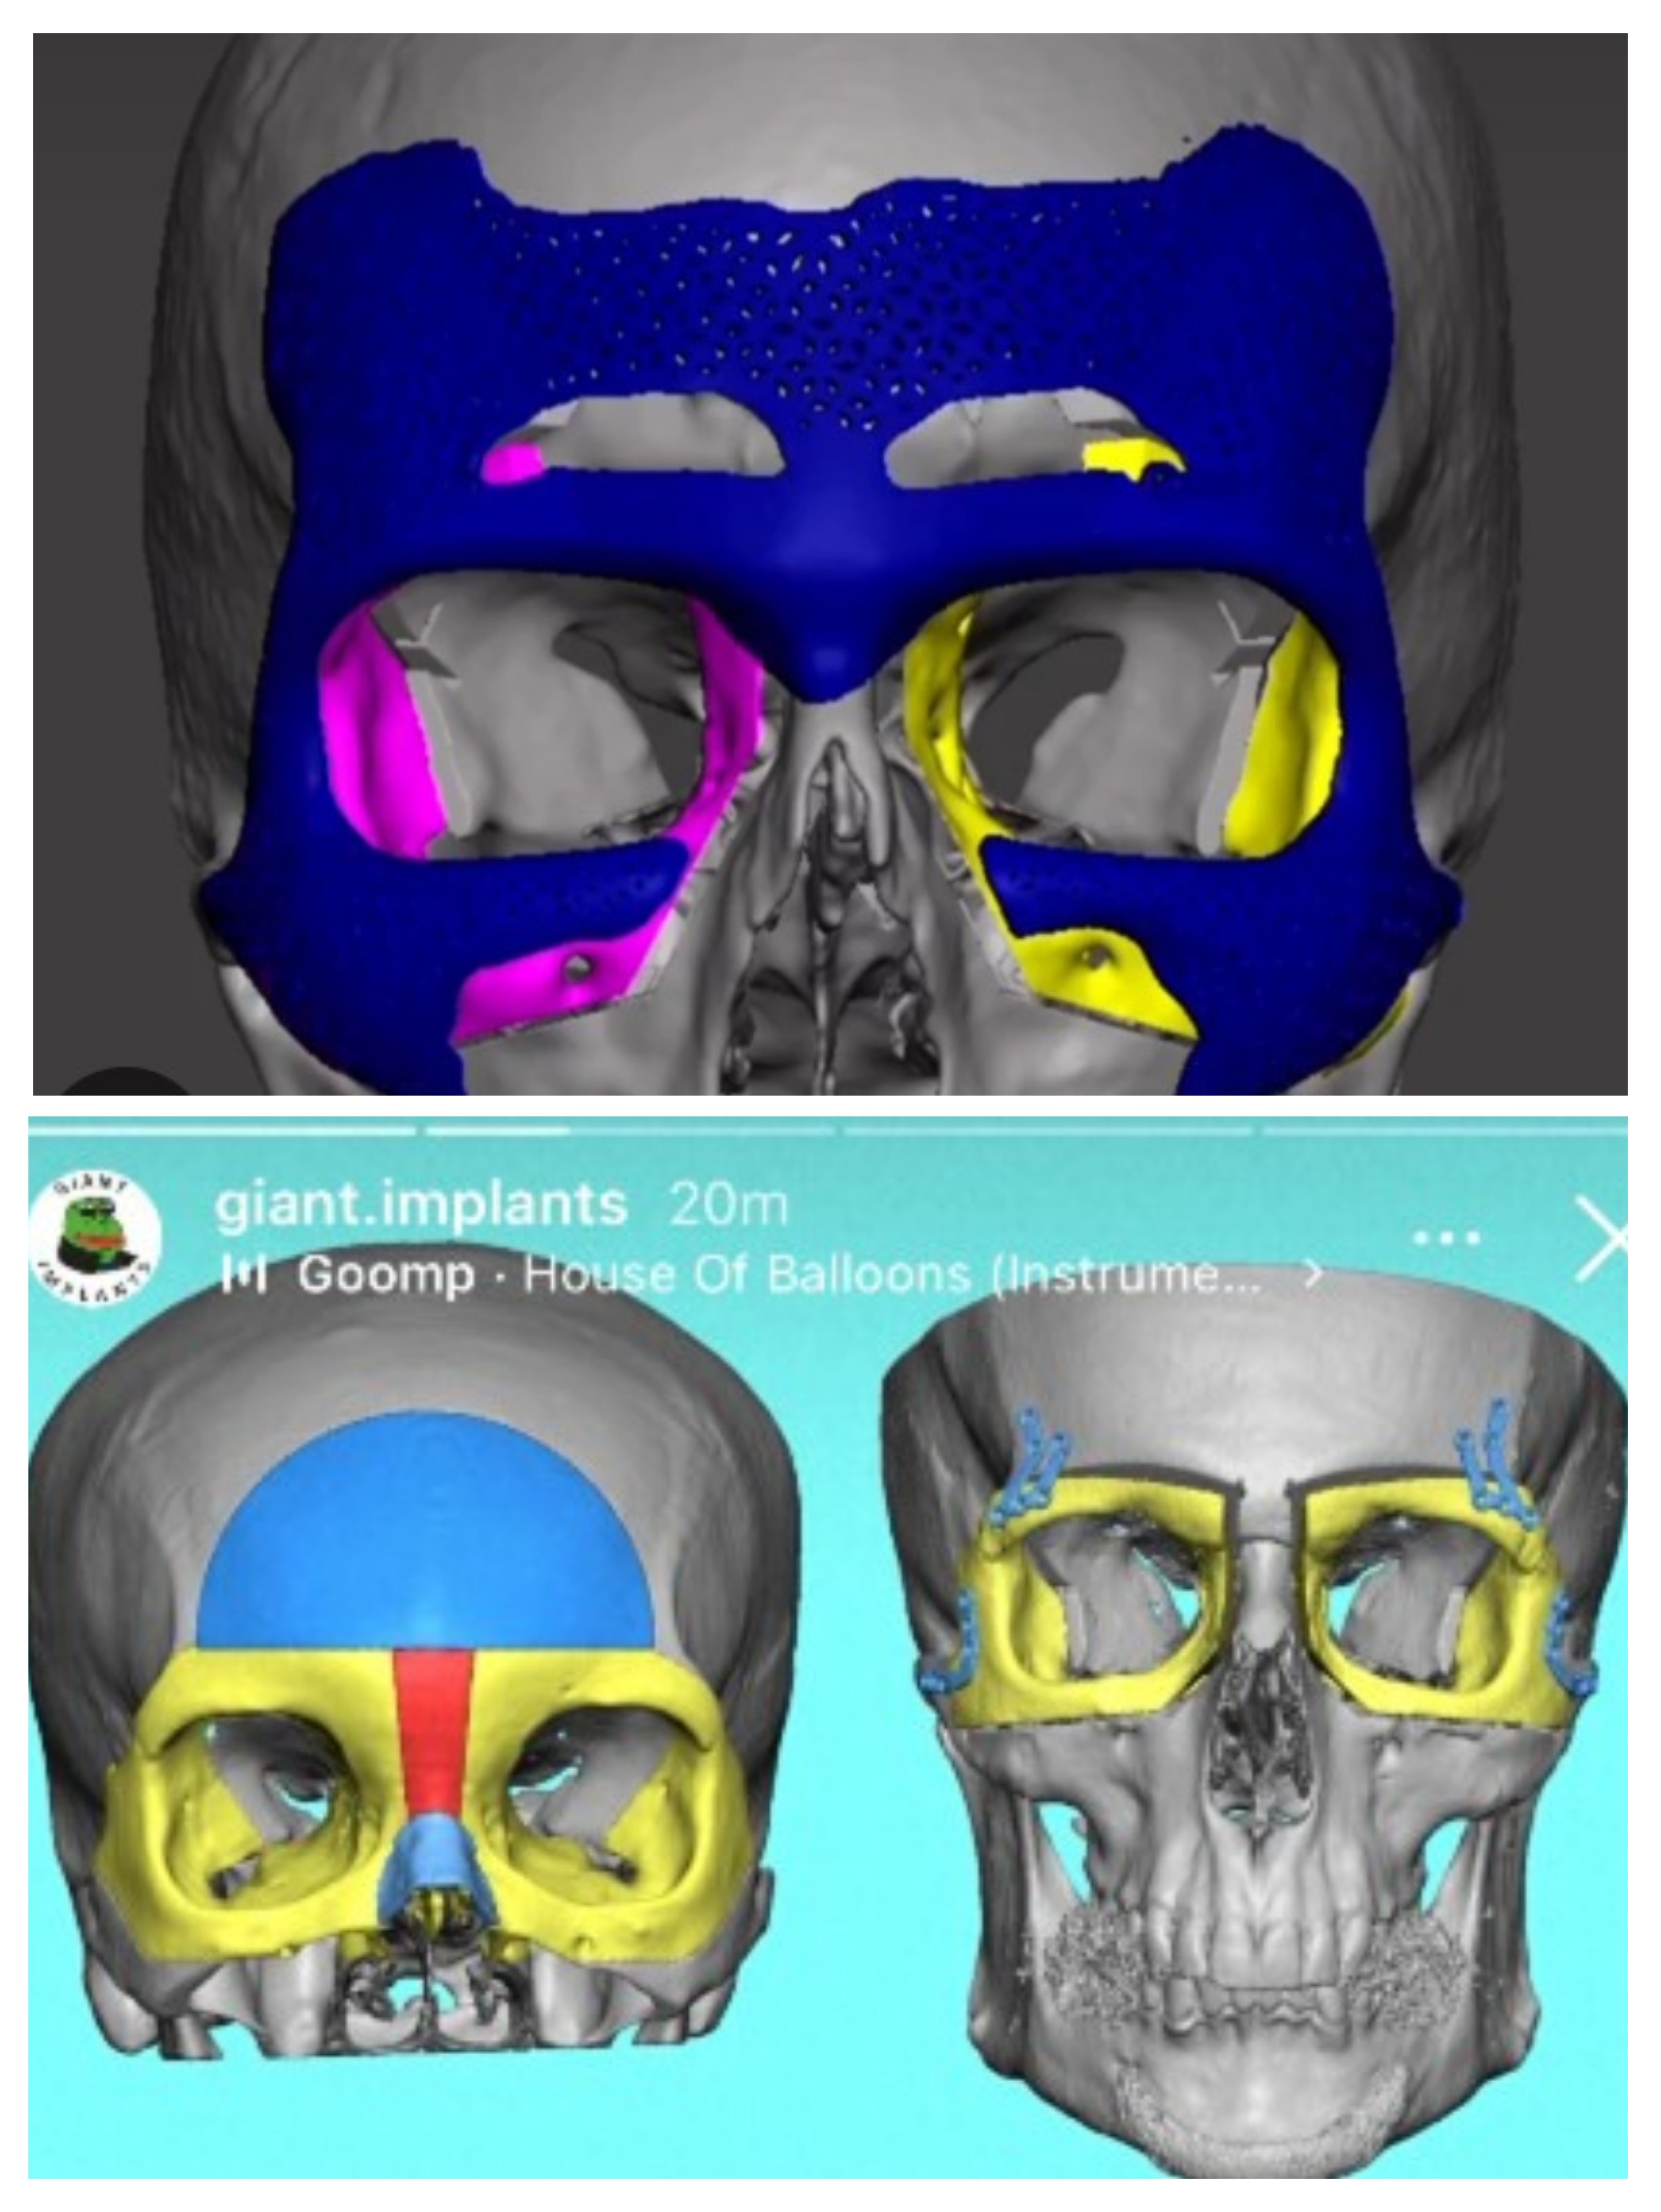

4. Full face custom implants

Hunter skull illusion

4. Full face custom implants

Hunter skull illusion